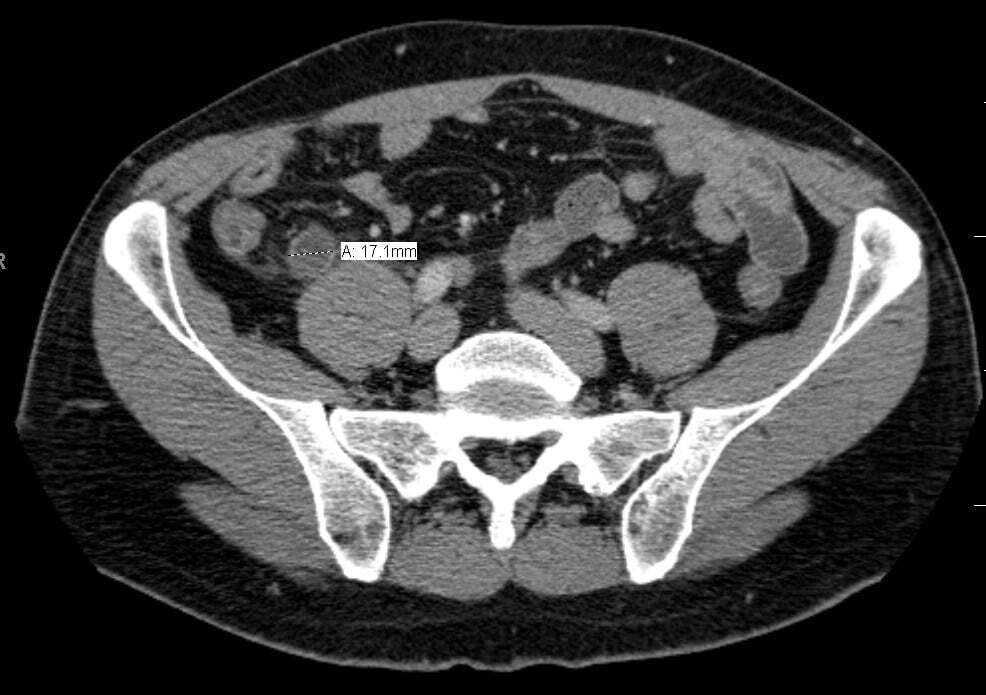

CT can be useful if another diagnosis is more likely

What imaging is done for appendicitis?

Imaging can be used to confirm diagnosis